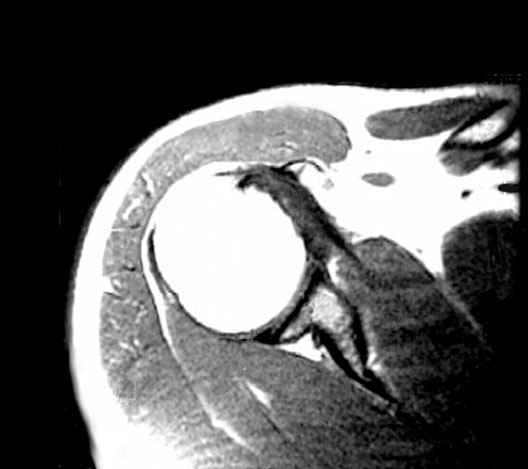

Shoulder MRI

Roll mouse over image to display labels.

1. Infraspinatus

2. Teres minor

3. Glenoid labrum

4. Deltoid

5. Head of the humerus

6. Tendon of the long head of biceps

7. Subscapularis

8. Axilla

9. Pectoralis major

10. Clavicle